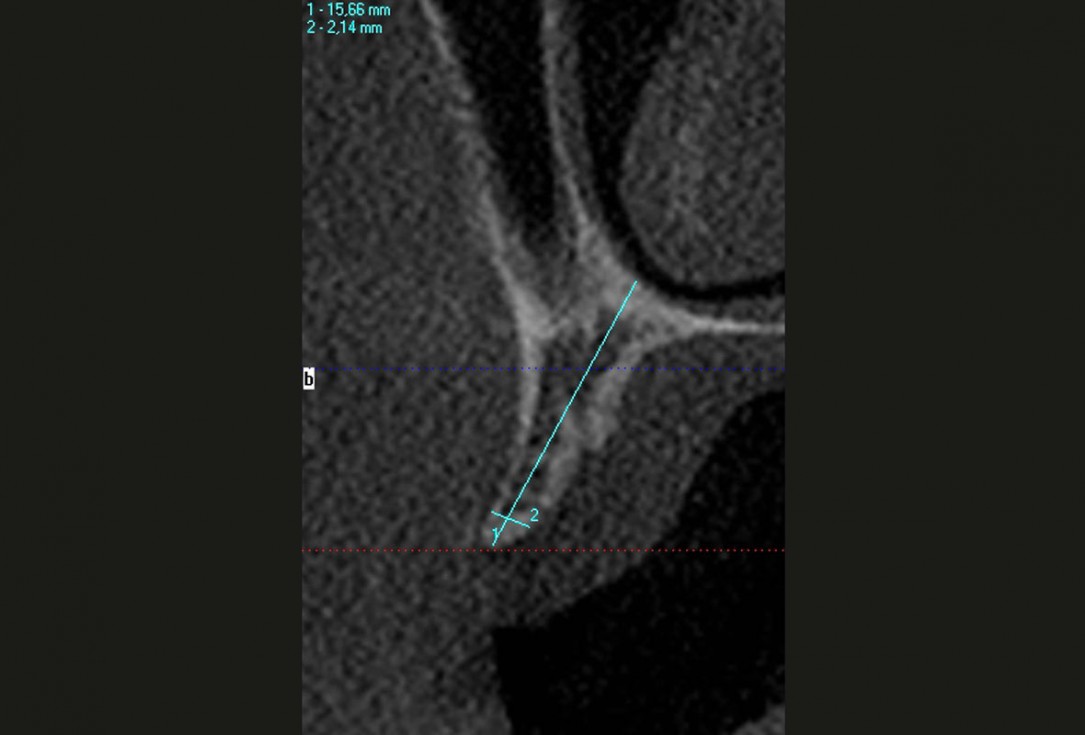

Ridge augmentation in the maxilla with maxgraft® bonebuilder in the aesthetic zone - Dr. M. Kristensen

Bone defect in area 11-21 due to two lost implants (periimplantitis) after 15 years of function